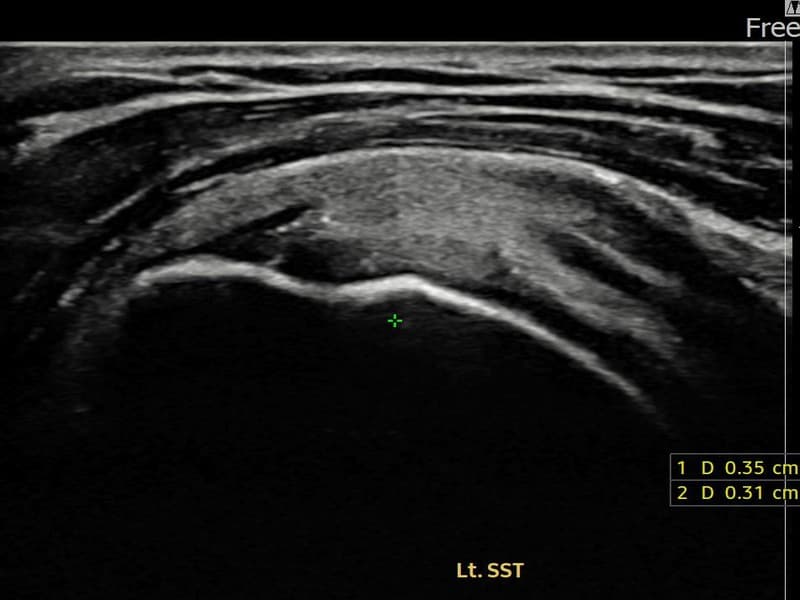

시술 전 초음파 측정 결과 파열 크기는 5mm × 3mm (힘줄 두께의 약 25% 결손)로 확인되었습니다. 시술 전 초음파에서 좌측 극상근건 부착부의 에코 단절과 힘줄 결손 소견이 확인되었습니다. 시술 후 초음파에서 부착부 연속성이 회복되고 결손 부위에 재생 조직이 형성된 것이 관찰되었습니다.

50대 후반 여성 환자분으로, 왼쪽 어깨 부착부 통증이 지속되어 내원하셨습니다. 야간 통증이 심해 수면이 어렵고, 팔을 들어 올릴 때 날카로운 통증이 있어 일상 생활에 많은 불편함이 있으셨습니다. 초음파 검사에서 좌측 극상근건 부착부 부분파열이 확인되었으며, 초음파 유도 하 축소봉합술을 시행하였습니다. 시술 후 보조기 착용과 재활 운동을 통해 꾸준히 회복하였고, 시술 14주 후 추적 초음파에서 부착부 힘줄 연속성이 완전히 회복된 것이 확인되어 야간 통증이 소실되고 정상 수면이 가능해지셨습니다.